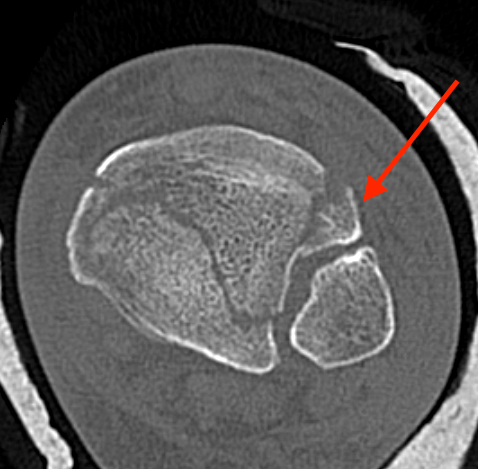

CT scan

Commonly 3 fracture configurations

- medial malleolus

- posterolateral fragment / Volkmann

- anterolateral fragment / Chaput

Tibial plafond common fragmentsTibial plafond fragments

Syndesmotic equivalent fractures tibial plafondChaput fragment syndesmotic equivalent

- syndesmotic equivalent injuries more common with Chaput (AITFL Ligament) / Volkmann fragments (PITFL) or fibular avulsion